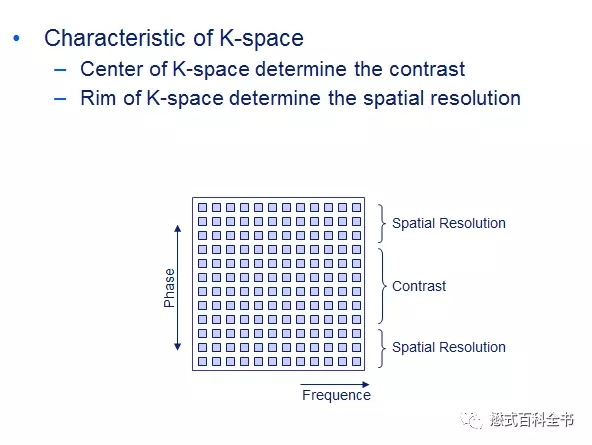

K空间除了具有对称性的特点外,最重要的另一个特性就是后处理后的图像特性。

K空间中心(中央)部分的数据,主要决定图像的对比度;

K空间周边(周围)部分的数据,主要决定图像的细节(空间分辨率)。

图13:把K空间所有的信息(中央部分和周边部分)都利用,重建后的图像是一个完整的图像。对比度和解剖细节都很好。

图14:只利用K空间中心部分数据来做图像重建,把周围数据丢弃掉。可以发现重建出来的图像,对比度比较好(基本上跟图13差不多),但是空间分辨率不够,解剖细节模糊。

图15:只利用K空间周边数据,把中心部分数据丢弃,来重建图像。可以发现,重建图例的图像,周围有轮廓,有解剖细节,但是没有对比度,无论是脑脊液和脑实质,还是灰质白质,都没有对比度。